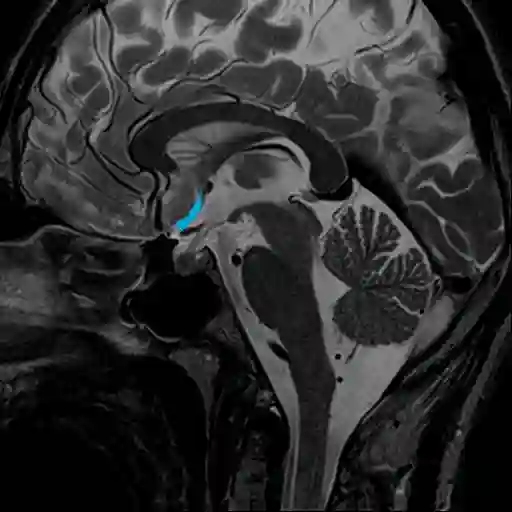

Cisterna laminae terminalis

Synonyme: Cistern of lamina terminalis

Die Cisterna laminae terminalis ist eine mit Liquor gefüllte Zisterne des Gehirns.

Die Cisterna laminae terminalis befindet sich zwischen dem Genu corporis callosi und oberer Chiasmafläche. Die Cisterna laminae terminalis steht mit der Cisterna chiasmatica, der Cisterna olfactoria und der Cisterna pericallosa in Verbindung. In manchen Fällen kann die Cisterna laminae terminalis von der Cisterna chiasmatica durch ein Septum getrennt sein[^1]. In der Cisterna laminae terminalis verläuft die Arteria cerebri anterior und die Arteria communicans anterior samt den Arteriae centrales anteromediales[^1].

Darstellung der Cisterna laminae terminalis (in blau markiert) in einer sagittalen T2 MRT Bildsequenz.